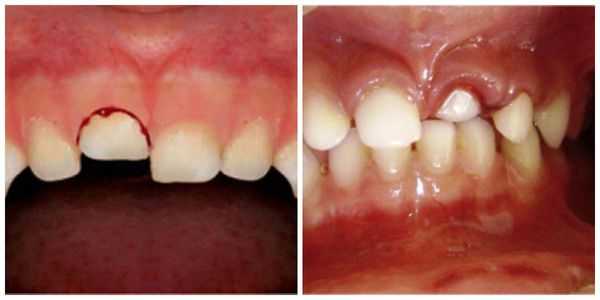

- Полный вывих: сопровождается сильной болью; зуб в лунке отсутствует; пустая лунка кровоточит; десна изменена в цвете; имеется припухлость; может возникнуть гематома; происходит локальное повышение температуры; некоторое время могут наблюдаться дефекты речи.

Полный вывих характеризуется полным разрывом волокнистых структур периодонта (в том числе круговой связки зуба). При этом травмированный зуб в лунке отсутствует, а сосудисто-нервный пучок зуба всегда разрывается. Вывих может сопровождаться переломом края альвеолы. Иногда зуб может присутствовать в альвеоле за счёт единичных сохранившихся волокон круговой связки. По статистике полному вывиху чаще подвергаются фронтальные зубы верхней челюсти, реже — нижней. Меньше других подвержены полному вывиху клыки.

Лечение полного вывиха

В случае полного вывиха зуба, если с момента травмы прошло не более двух суток, проводится его реплантация (установка зуба обратно в лунку) [8] .

Чем раньше проводится реплантация, тем выше вероятность положительного результата. Резорбция корня в данной ситуации менее выражена и протекает медленнее.

Реплантацию проводят по общепринятой методике:

- Травмированный зуб промывают и помещают в изотонический раствор натрия хлорида с антибиотиками до самой операции.

- Если после вывиха прошло не более 10 часов, можно реплантировать зуб, не проводя эндодонтическое лечение (лечение корневых каналов). В таком случае эндодонтическое лечение зуба проводят через 2-3 недели после реплантации, когда становится очевидным приживление зуба.

- Если с момента вывиха прошло более 10 часов, пульпу полностью удаляют, а канал после механической и медикаментозной обработки пломбируют. Зуб после реплантации выводят из прикуса и укрепляют путём шинирования с помощью пластмассовой шины-каппы. Снимают её только через 3-4 недели.

- После реплантации необходимо в течение от одного до двенадцати месяцев проводить рентгенологический контроль. Это позволяет судить о состоянии корня зуба, периодонта и кости.

Необходимо отметить, что самые благоприятные результаты получены при проведении реплантации через 20-30 минут после вывиха.